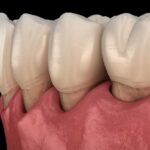

Em uma mordida normal, os dentes superiores cobrem levemente os inferiores. Já na mordida cruzada, alguns dentes superiores ficam para dentro da linha dos dentes inferiores.

- Mordida cruzada anterior

Os dentes da frente (anteriores) são sobrepostos pelos dentes inferiores.

- Mordida cruzada posterior

O posicionamento dos dentes de trás (posteriores) é afetado pela mordida cruzada. Esteticamente este problema é menos perceptível, mas pode ocasionar problemas de mastigação, quebra de dentes, dificuldade de higienização, cáries e doenças gengivais.

Mordida cruzada antes do tratamento com invisalign